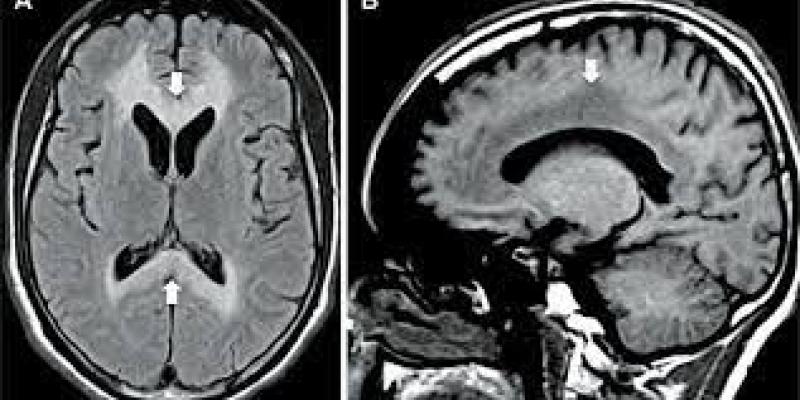

La enfermedad de Marchiafava-Bignami (EMB) es una condición rara asociada principalmente con el alcoholismo, aunque no exclusivamente. Se caracteriza por una desmielinización y necrosis del cuerpo calloso con la subsiguiente atrofia, es decir, provoca una erosión del cuerpo calloso.